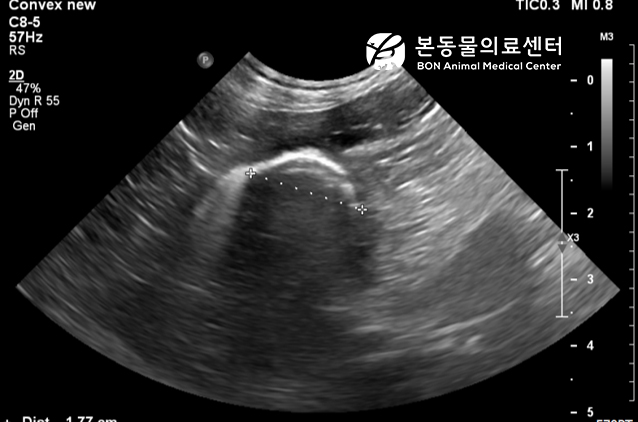

복부 초음파 검사

복부 방사선 사진 상 점선처럼 씨앗 의심 구조가 확인되고, 초음파 검사 시 형태 (curved-linear structure) 등을 고려 시 위 내 씨앗 이물이 저류된 것으로 강하게 의심되어 우선 구토 처치를 실시하였다.